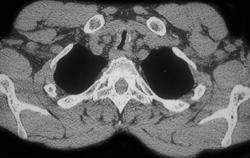

Ductus Aneurysm